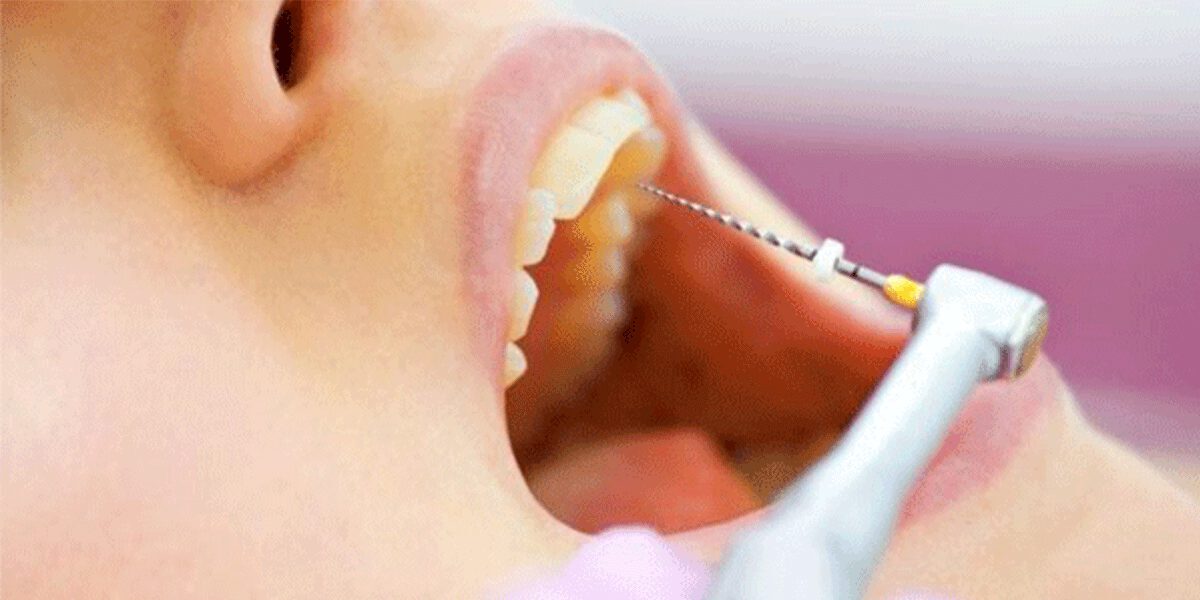

عامل دیگر، موقعیت جغرافیایی کلینیک است. طبیعتاً قیمت عصب کشی دندان در تهران و کلینیکهای مناطق مرکزی و شمال شهر، به دلیل هزینههای بالاتر اجاره و تجهیزات، میتواند با شهرستانها یا مناطق دیگر تفاوت داشته باشد. همچنین، تخصص و تجربه دندانپزشک نقش مهمی ایفا میکند. یک متخصص درمان ریشه (اندودنتیست) که سالها به طور تخصصی روی این حوزه کار کرده، طبیعتاً هزینه بیشتری نسبت به یک دندانپزشک عمومی برای یک درمان پیچیده دریافت میکند، اما شانس موفقیت درمان نیز بالاتر میرود. استفاده از تکنولوژیهای پیشرفته مانند دستگاه روتاری (برای تمیز کردن کانالها)، میکروسکوپ و رادیوگرافی دیجیتال، دقت کار را به شدت افزایش داده و ماندگاری درمان را بالاتر میبرد، اما به همان نسبت بر قیمت عصب کشی دندان میافزاید.